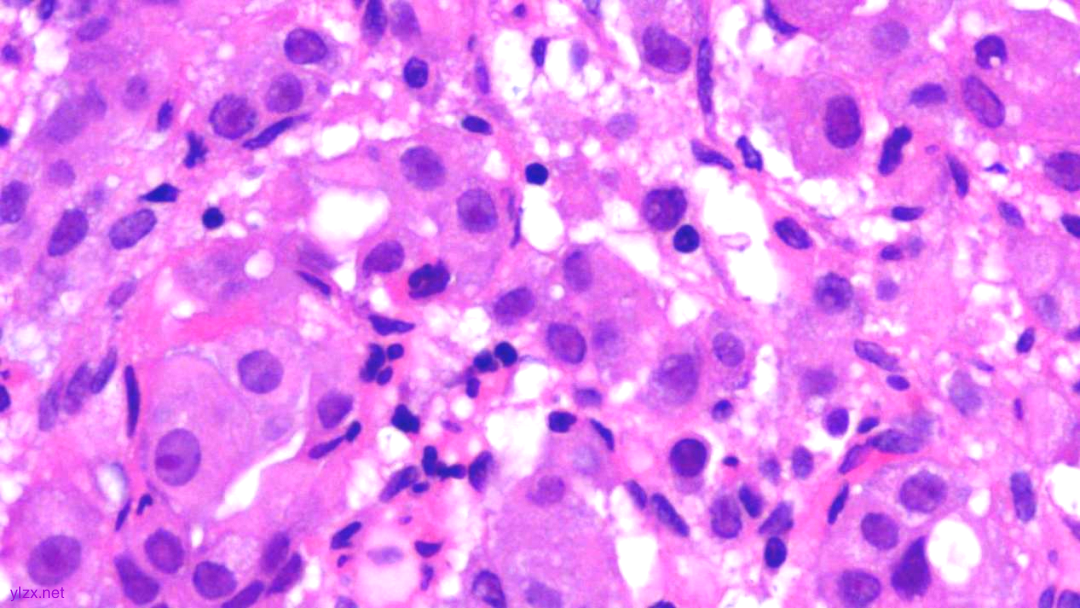

HE:

黏膜间质内见胞浆丰富,红染及粉染瘤细胞弥漫分布,部分细胞核稍偏位,核圆形,稍增大,深染,见核仁,穿插在固有腺之间,伴少量炎细胞浸润。

瘤组织穿插在固有腺之间,较弥漫,核稍增大,深染

瘤细胞稀疏排列,胞浆粉染及红染,宽阔

瘤细胞核圆形,见核仁,部分细胞核偏位,未见核分裂象

瘤细胞核仁明显